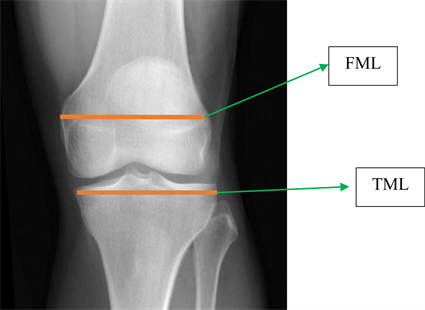

Totally, 14 dimensions measured and DICOM program used for measuring (dimensions demonstrated by mm) (Figure 1, Figure 2).

Figure 1. Dimensions of FML and TML X-ray (Femur medial lateral (FML) Tibia medial lateral (TML)).